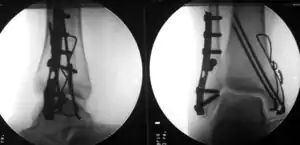

Fracture of both sides of the ankle with dislocation as seen on anteroposterior X-ray. (1) fibula, (2) tibia, (arrow) medial malleolus, (arrowhead) lateral malleolus

Surgically fixated bimalleolar ankle fracture

The broad goals of treating ankle fractures are restoring the ankle joint to normal alignment, healing the fracture, and preventing arthritis.[8] The stability of the ankle joint often dictates treatment. Certain fracture patterns are stable and are thus treated without surgery similarly to ankle sprains. Unstable fractures require surgery, most often an open reduction and internal fixation (ORIF), which is usually performed with permanently implanted metal hardware that holds the bones in place while the natural healing process occurs. A cast or splint will be required to immobilize the ankle following surgery.[11] Stable ankle fractures with preserved joint alignment may be treated with non-operative measures (splinting, casting, and/or walking boot).[11]